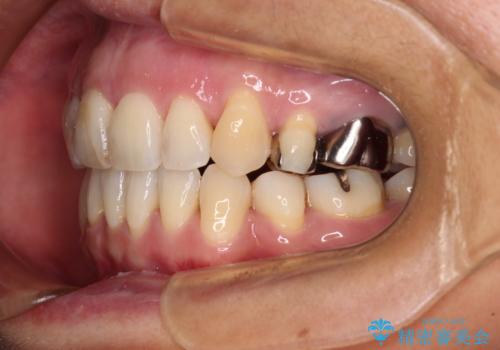

半年もしないうちに八重歯は解消し、治療も当初予定通り2年強で終えることができました。

八重歯・デコボコの解消とともに、前方に張り出した上顎前歯を引っ込めることを目的とし、上下左右の第一小臼歯4歯を抜歯をしてワイヤー矯正により治療することとしました。